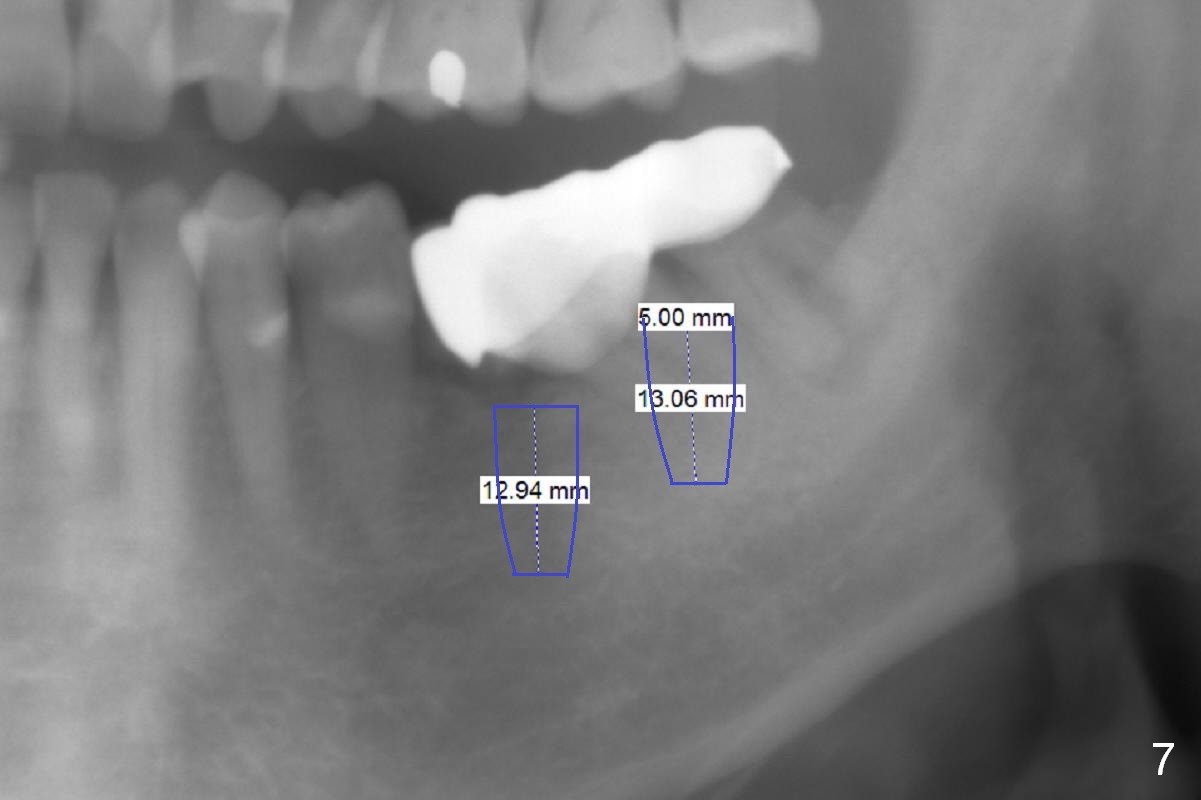

A 82-year-old man has pain in the lower left bridge. There is a buccal apical fistula associated with the tooth #17 (Fig.1). An immediate implant will be placed at #17 after bridge removal (Fig.2,3 blue). Once it osteointegrates, it will be used an anchorage (direct (instead of indirect), most efficient) to upright the tooth #18 (change the longitudinal axis from red line to purple one (Fig.4); white circle: center of resistance (rotation)). Then an implant will be placed at #19 (white rectangle).

Take Alginate impression and keep it moist. It will be used as a stent for temporization later on. After the tooth #17 is extracted with Clindamycin treatment, a FC dummy implant (5x9 mm) will be placed, followed by 6x4(2) mm abutment (Fig.3,4 pink). If there is severe vertical height issue, change to Magicore. Due to schedule conflict, prepare UF for this case instead.